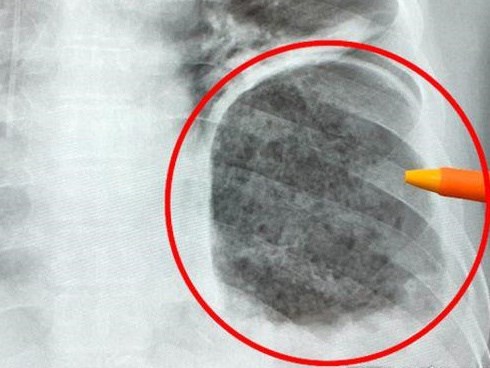

Phát hiện hai bệnh ung thư cùng lúc từ dấu hiệu đau thắt lưng

Từ dấu hiệu đau thắt lưng tăng dần, ông S. quyết định đi khám. Tại Bệnh viện Bạch Mai, các bác sĩ chẩn đoán ông mắc cùng lúc hai bệnh ung thư, đã di căn sang xương.